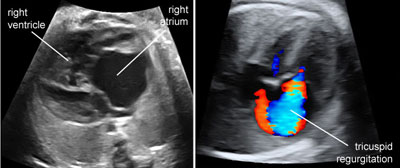

Ebstein malformation of the tricuspid valve

Legend:Ebstein malformation of the tricuspid valve: the leaflets of the tricuspid valve are displaced apically compared to the atrioventricular junction and there is massive tricuspid regurgitation

Tricuspid dysplasia

Legend:Cardiomegaly, enlargement of the right side of the heart and right atrium in particular, massive regurgitation across a normally inserted tricuspid valve